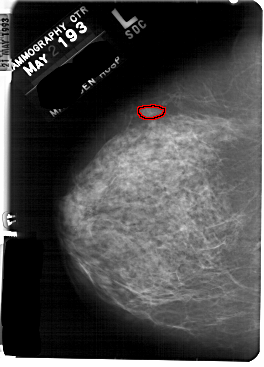

FILE: A_1834_1.LEFT_CC.OVERLAY

TOTAL_ABNORMALITIES 1

ABNORMALITY 1

LESION_TYPE MASS SHAPE LOBULATED MARGINS OBSCURED

ASSESSMENT 4

SUBTLETY 4

PATHOLOGY BENIGN

TOTAL_OUTLINES 1

BOUNDARY

LEFT_CC LINES 5491 PIXELS_PER_LINE 3946 BITS_PER_PIXEL 12 RESOLUTION 43.5 OVERLAY